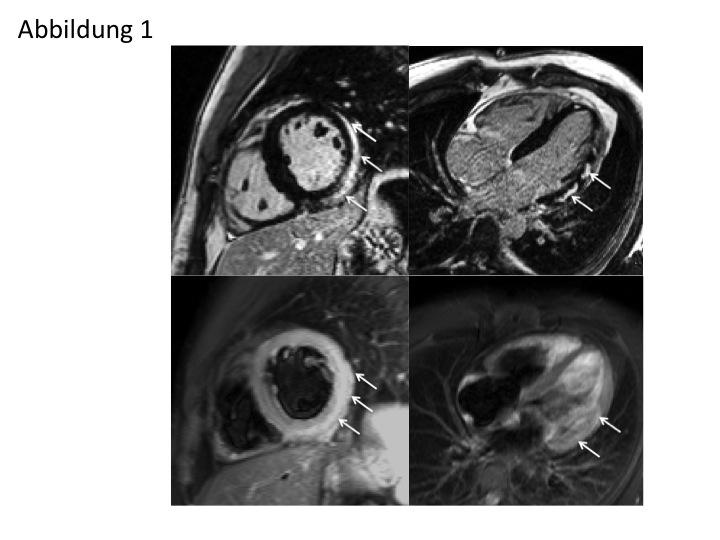

Abb. 1: 29-jähriger Patient mit Infekt der oberen Atemwege. Im Verlauf akute Brustschmerzen, ST-Hebungen im EKG und deutlich erhöhte Herzenzyme, in der Herzkatheteruntersuchung Ausschluss KHK. Jetzt CMR mit der Frage nach Myokarditis. Im LGE (obere Reihe) Nachweis von teils fleckigem, von epikardial ausgehendem LGE (hell, s. Pfeile) ohne Beteiligung der subendokardialen Schichten, Befund typisch für Myokarditis. Darstellung in der kurzen Herzachse (SAX), im Vierkammerblick (4CV). Korrespondierende T2-Sequenzen in der unteren Reihe: Die signalreichen Areale (verlängerten T2-Werten entsprechend) zeigen eine gewisse Übereinstimmung zu den Signalanreicherungen der LGE-Sequenzen in der oberen Reihe, s. Pfeile, lassen sich aber insgesamt deutlich schlechter abgrenzen als in den LGE-Bildern (Foto: Robert-Bosch-Krankenhaus Stuttgart).